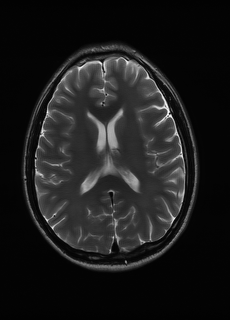

As we observe from the right image in Fig. 2, our BRM, both from MIMO and SISO settings, predicts the performance of dedicated models with a high correlation. We further choose the best three , and perform the last stage of fine-tuning accordingly to (6). A visual evaluation on real data is shown in Fig. 3. For simulated data, please refer to the Supplemental Material section.

Base on the best performing , we perceive that among , , and FLAIR, the results are best when is sampled the most. We suggest that this makes intuitive sense as images provide the best contrast out of the three sequences, which can compensate for the details lost in other images. The same observation can be made on the simulated data, where both and FLAIR show good contrast. When the time setting is changed to non-uniformity, we can see that our search for the best sampling strategy reflects the change. is sampled more as a result of faster acquisition time, while is still sufficiently sampled.

| Sequence | LR | SISO | MIMO | MIMO tuned | GT |

|---|---|---|---|---|---|

(a) 34.38/0.9371

(a) 34.38/0.9371

|

(b) 42.42/0.9883

(b) 42.42/0.9883

|

(c) 44.60/0.9920

(c) 44.60/0.9920

|

(d) 45.50/0.9940

(d) 45.50/0.9940

|

(e) PSNR/SSIM

(e) PSNR/SSIM

|

|

(f) 29.74/0.8903

(f) 29.74/0.8903

|

(g) 36.25/0.9734

(g) 36.25/0.9734

|

(h) 36.42/0.9752

(h) 36.42/0.9752

|

(i) 37.70/0.9832

(i) 37.70/0.9832

|

(j) PSNR/SSIM

(j) PSNR/SSIM

|

|

(k) 39.89/0.9311

(k) 39.89/0.9311

|

(l) 43.94/0.9864

(l) 43.94/0.9864

|

(m) 44.74/0.9883

(m) 44.74/0.9883

|

(n) 45.49/0.9894

(n) 45.49/0.9894

|

(o) PSNR/SSIM

(o) PSNR/SSIM

|